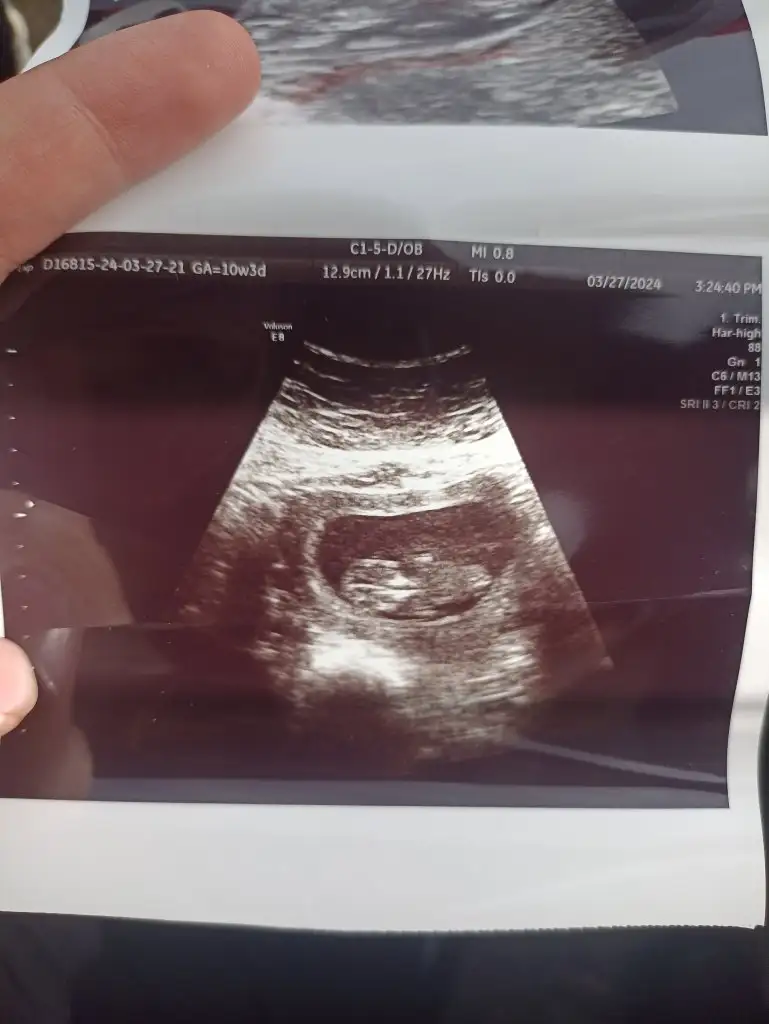

Banada bakarmısınız 10+3 :)Bana kız gibi geldi bebeğiniz bidaha giderseniz atarsınız bakarım

Merhaba sırtını dönmüş bebeğiniz başka var mı ultrasonBanada bakarmısınız 10+3 :)

Attım cnm demin benden sonra biri daha attığı için görmemis olabilirsinizAtın bakayım

Tam kıza benziyo sizinkiAttım cnm demin benden sonra biri daha attığı için görmemis olabilirsiniz